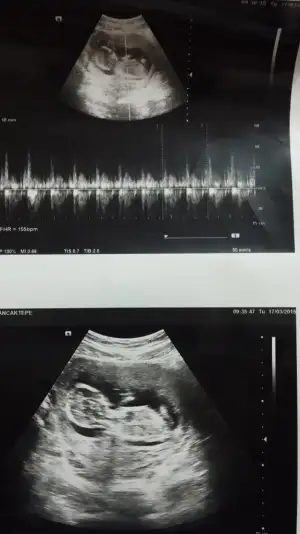

Yeni ultrasonumuz hala belli değil 11+2 olduk yorumlarmısınız rica etsem

11 haftalik ken foto yuklemistim cinsiyetimiz kesinleşti erkekmis hepinize teşekkür ederim